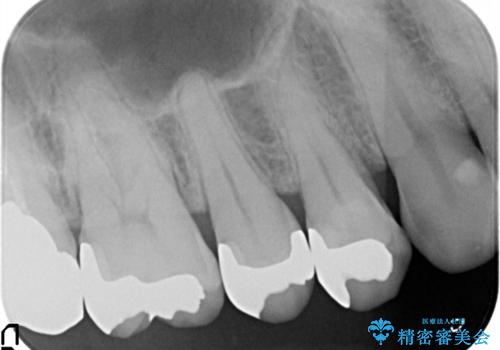

- 定期健診にてむし歯を認めたためゴールドインレーにて治療を行いました。

ゴールドインレーは適合が良く、割れることもないため、長期的に安定した治療法となります。